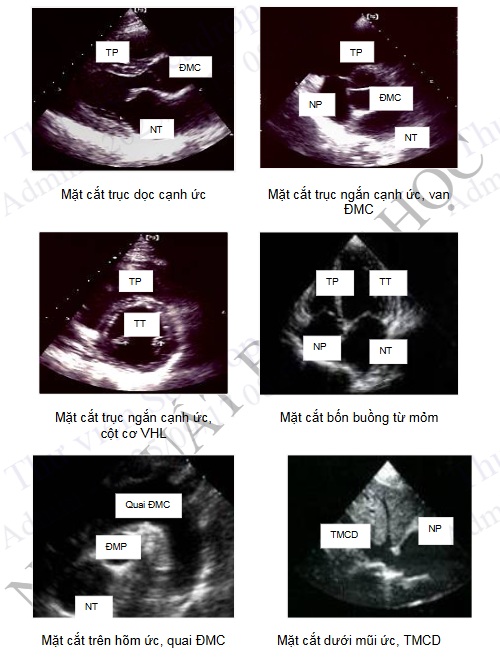

Bước đầu tiên là các vị trí và tư thế đặt đầu dò. Có 4 vị trí đặt đầu dò theo thứ tự là: vị trí trên hõm ức, cạnh ức trái, mỏm tim và dưới mũi ức.

Mặt cắt siêu âm được chia làm 3 loại: + Mặt cắt trục dài tương ứng với trục dọc của thất trái và vuông góc với mặt phẳng đứng ngang của cơ thể. + Mặt cắt trục ngắn làm mặt cắt vuông góc với mặt cắt trục dài và cắt qua trục ngang của thất trái. + Mặt cắt 4 buồng cũng theo hướng trục dọc của thất trái nhưng song song với mặt cắt đứng ngang. buồng

Hội Siêu âm tim Mỹ đã thống nhất tên gọi các cho các hình ảnh là phối hợp giữa vị trí đặt đầu dò và mặt cắt siêu âm. Ví dụ hình ảnh có được từ mặt cắt trục ngắn với đầu dò đặt ở cạnh ức trái được gọi là hình ảnh cắt ở mặt cắt trục ngắn cạnh ức trái.

Vị trí trên hõm ức cho phép đánh giá động mạch chủ lên, quai động mạch chủ và động mạch chủ xuống ở mặt cắt trục dọc và trục ngắn.

Mặt cắt trục ngắn cạnh ức cho phép đánh giá thất trái theo mặt cắt ngang, mặt cắt trục dọc cạnh ức cho phép đánh giá đường ra thất trái, van hai lá và van động mạch chủ, nhĩ trái, thất phải, vùng trước vách, vùng mỏm và vùng thành sau thất trái.

Ở vị trí mỏm tim có thể đánh giá được tim ở mặt cắt hai buồng, ba buồng, bốn buồng và năm buồng tim.

Vị trí dưới mũi ức rất có ích ở bệnh nhân có bệnh phổi làm cản trở siêu âm trước thành ngực. Ngoài thăm khám tim mặt cắt trục dọc và trục ngắn, vị trí cửa sổ này giúp đánh giá tốt tĩnh mạch gan, tĩnh mạch chủ dưới và vách liên nhĩ.

Hình 4.78. Hình ảnh siêu âm tim 2D một số mặt cắt cơ bản (TT: thất trái, NT: nhĩ trái, ĐMC: động mạch chủ, TP: thất phải, NP: nhĩ phải, ĐMP: động mạch phổi)